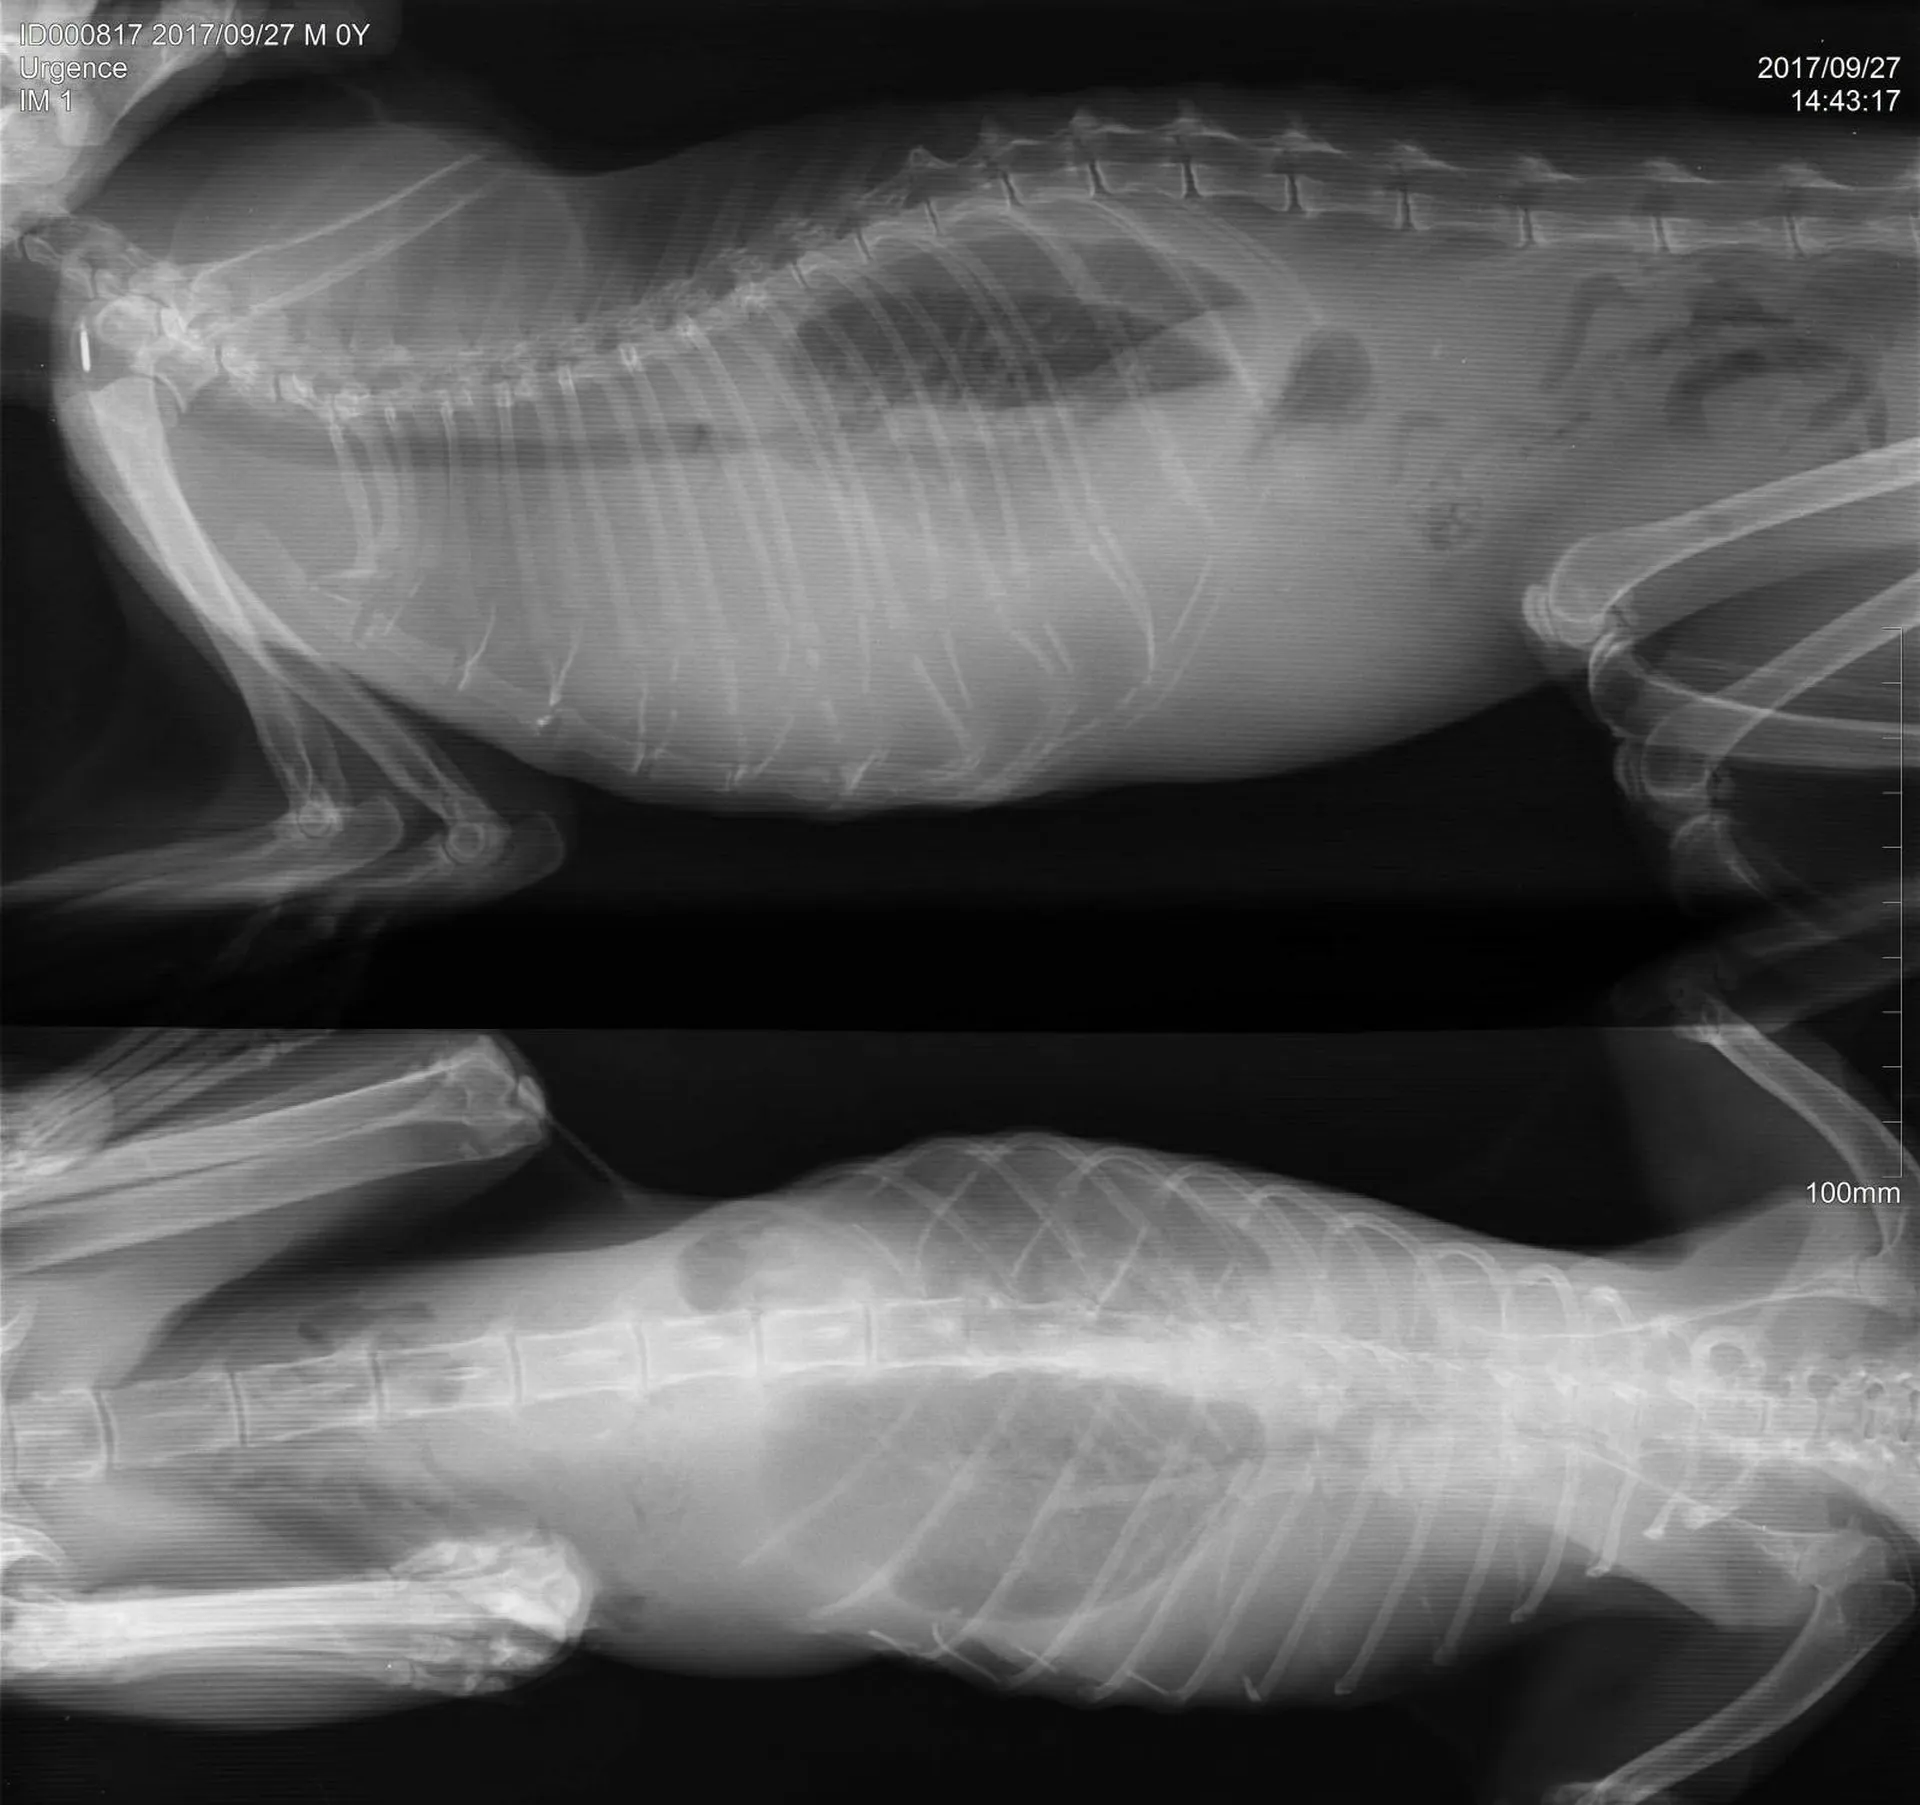

Une radiographie est un examen d’imagerie consistant à la prise de cliché au moyen d’un appareil à rayon X ceci afin de visualiser les différentes structures internes.

La radiographie reste indiquée dans de nombreuses affections, quelles soient respiratoires (radiographie cervicale ou thoracique), digestives (radiographie thoracique ou abdominale), locomotrices (membres, colonne), dentaires.

Votre chien, chat Nac est déposé sur la table de radiologie et différents clichés sont effectués dans différentes positions suivant la pathologie présentée.

Comme tout examen, il présente ses limites. Le principe de la radiographie étant l’utilisation du contraste (visualisation d’un tissu par rapport au tissu environnant et par rapport à sa radiodensité), certaines pathologies ne peuvent être que suspectées par radiographie mais nécessite d’autres examens (échographie, endoscopie, scanner, IRM).